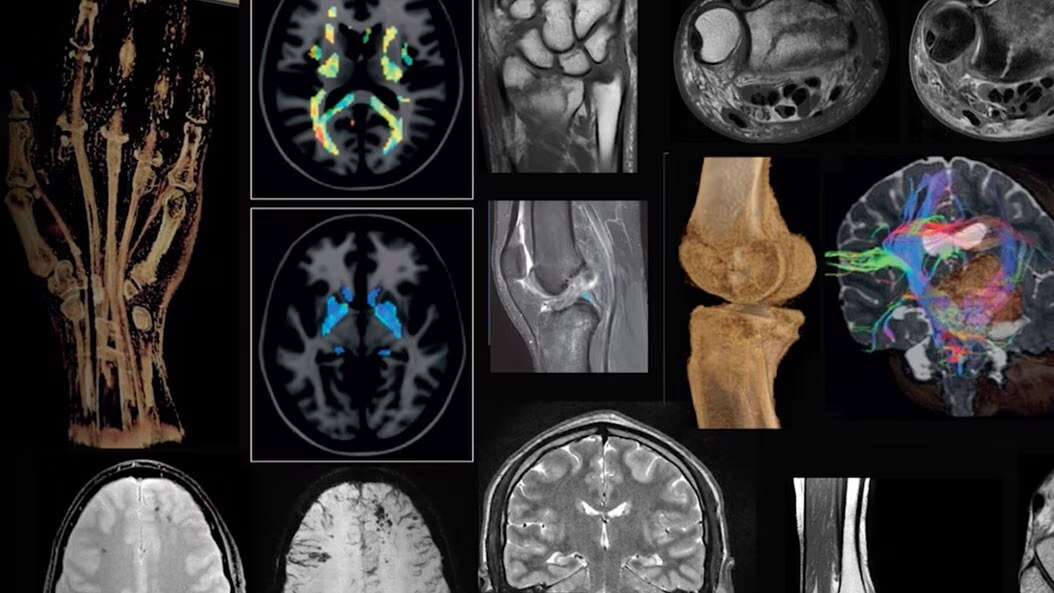

MRI applications for SIGNA

Comprehensive, upgradeable and customizable MR imaging platform for fast and flexible scanning across clinical specialties.